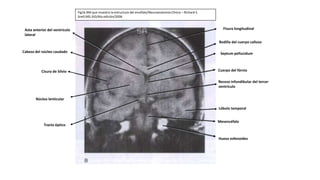

Fig16.RM que muestra la estructura del encéfalo/Neuroanatomía Clínica – Richard S.

Snell,MD.JhD/6ta edición/2006

Fisura longitudinal

Rodilla del cuerpo calloso

Septum pellucidum

Cuerpo del fórnix

Receso infundibular del tercer

ventrículo

Lóbulo temporal

Mesencéfalo

Hueso esfenoides

Asta anterior del ventrículo

lateral

Cabeza del núcleo caudado

Cisura de Silvio

Núcleo lenticular

Tracto óptico